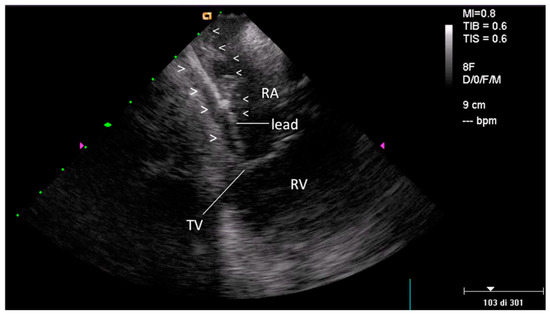

2.2.1. Before Extraction

3.1. Pre-extraction